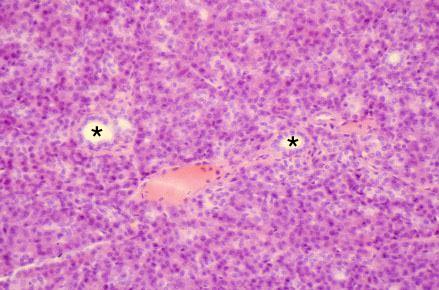

VIII-23, Slide 68, Pancreas (H&E). Serous pancreatic acinar cells and intralobular ducts (*) are present. The pancreas does not contain striated ducts.